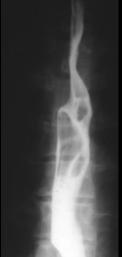

Image radiologique du transit

oesophagien d'un oesophagite caustique . C'est image

de stenose cicatricielle tres etendu de 2/3

inferierure oesophage |